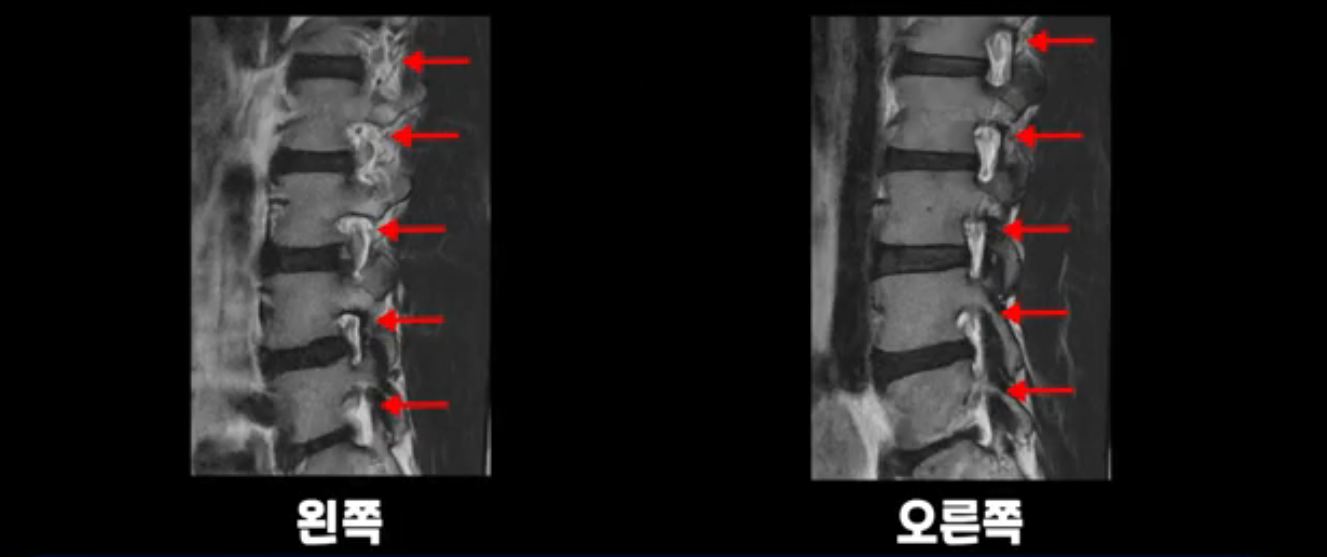

추간공도 보시다시피 왼쪽, 오른쪽 전부 다 매우 넓어서 신경이 눌릴만한 부분이 전혀 보이지 않습니다.

앞서 1번 2번, 4번 5번, 5번 1번의 디스크가 찢어지고 조금 밀려 나온 게 최근에 찢어진 게 아니고 오래된 걸로 보인다고 말씀 드렸죠. 왜 그럴까요? 만약 급성으로 찢어진 것이라면 아주 심한 디스크성 통증이 있겠죠. 기침이나 재채기를 하면 심하게 아프고 허리를 조금만 구부리거나 비틀면 아주 날카로운 통증들이 생길 겁니다. 그런데 이분은 이런 증상이 전혀 아닙니다. 또 디스크의 밀려나온 정도도 전혀 심하지 않기 때문에 이분이 가지고 계신 양쪽 다리 저림, 특히 이분은 누워있을 때도 양쪽 발이 발가락까지 쑤신다고 하는데 이정도 디스크 때문에 그런 증상은 생길 수가 없는 겁니다. 이처럼 이분의 가벼운 디스크 탈출은 이미 오래 전에 진행되었고 섬유륜 자체는 이미 아문 상태인데도 디스크내장증을 진단받은 환자들 중에는 본인이 섬유륜 파열 환자라고 끝까지 믿는 분들이 많습니다. 다시 말하지만 디스크내장증이라는 진단을 받은 환자들을 보면 거의 전부 다 섬유륜 파열 증상이 아닙니다. 증상이 완전히 다릅니다. 진단이 애초에 잘못되면 어떤 치료를 받아도 좋아질 수 없습니다.

이분은 어떤 한 병원에서 디스크 내장증 얘기를 들으셨는데요. 여기 보시는 것처럼 4번 5번의 하얀 HIZ(High Intensity Zone)을 보고 디스크 내장증의 근거로 얘기하는 병원들이 있는데,

이 HIZ는 섬유륜이 찢어졌다가 이미 아문 뒤에도 얼마든지 보일 수 있는 흔적일 가능성이 있어서 재채기를 하면 아픈지, 허리를 구부릴 때 날카로운 통증이 생기는가 등의 증상으로 구별해야 하는데 MRI만 보고 HIZ가 보이면 그게 마치 통증의 원인인 것처럼 얘기하는 의사들이 있습니다. 이분 MRI를 자세히 보고 증상을 정말 자세히 들어본 의사가 있었더라면 다른 환자분들처럼 증상과 MRI가 일치하지 않는다는 얘기를 들을 수 있었을 텐데 이분은 그런 얘기는 듣지 못했습니다.